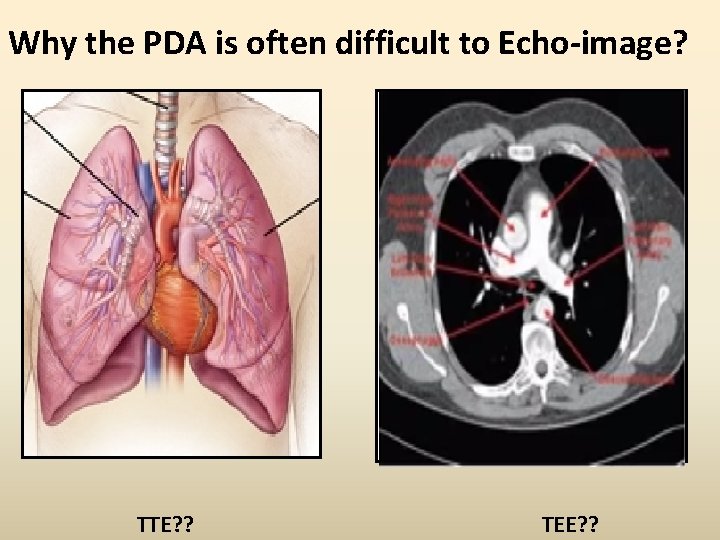

Why the PDA is often difficult to Echo-image? TTE? ? TEE? ?